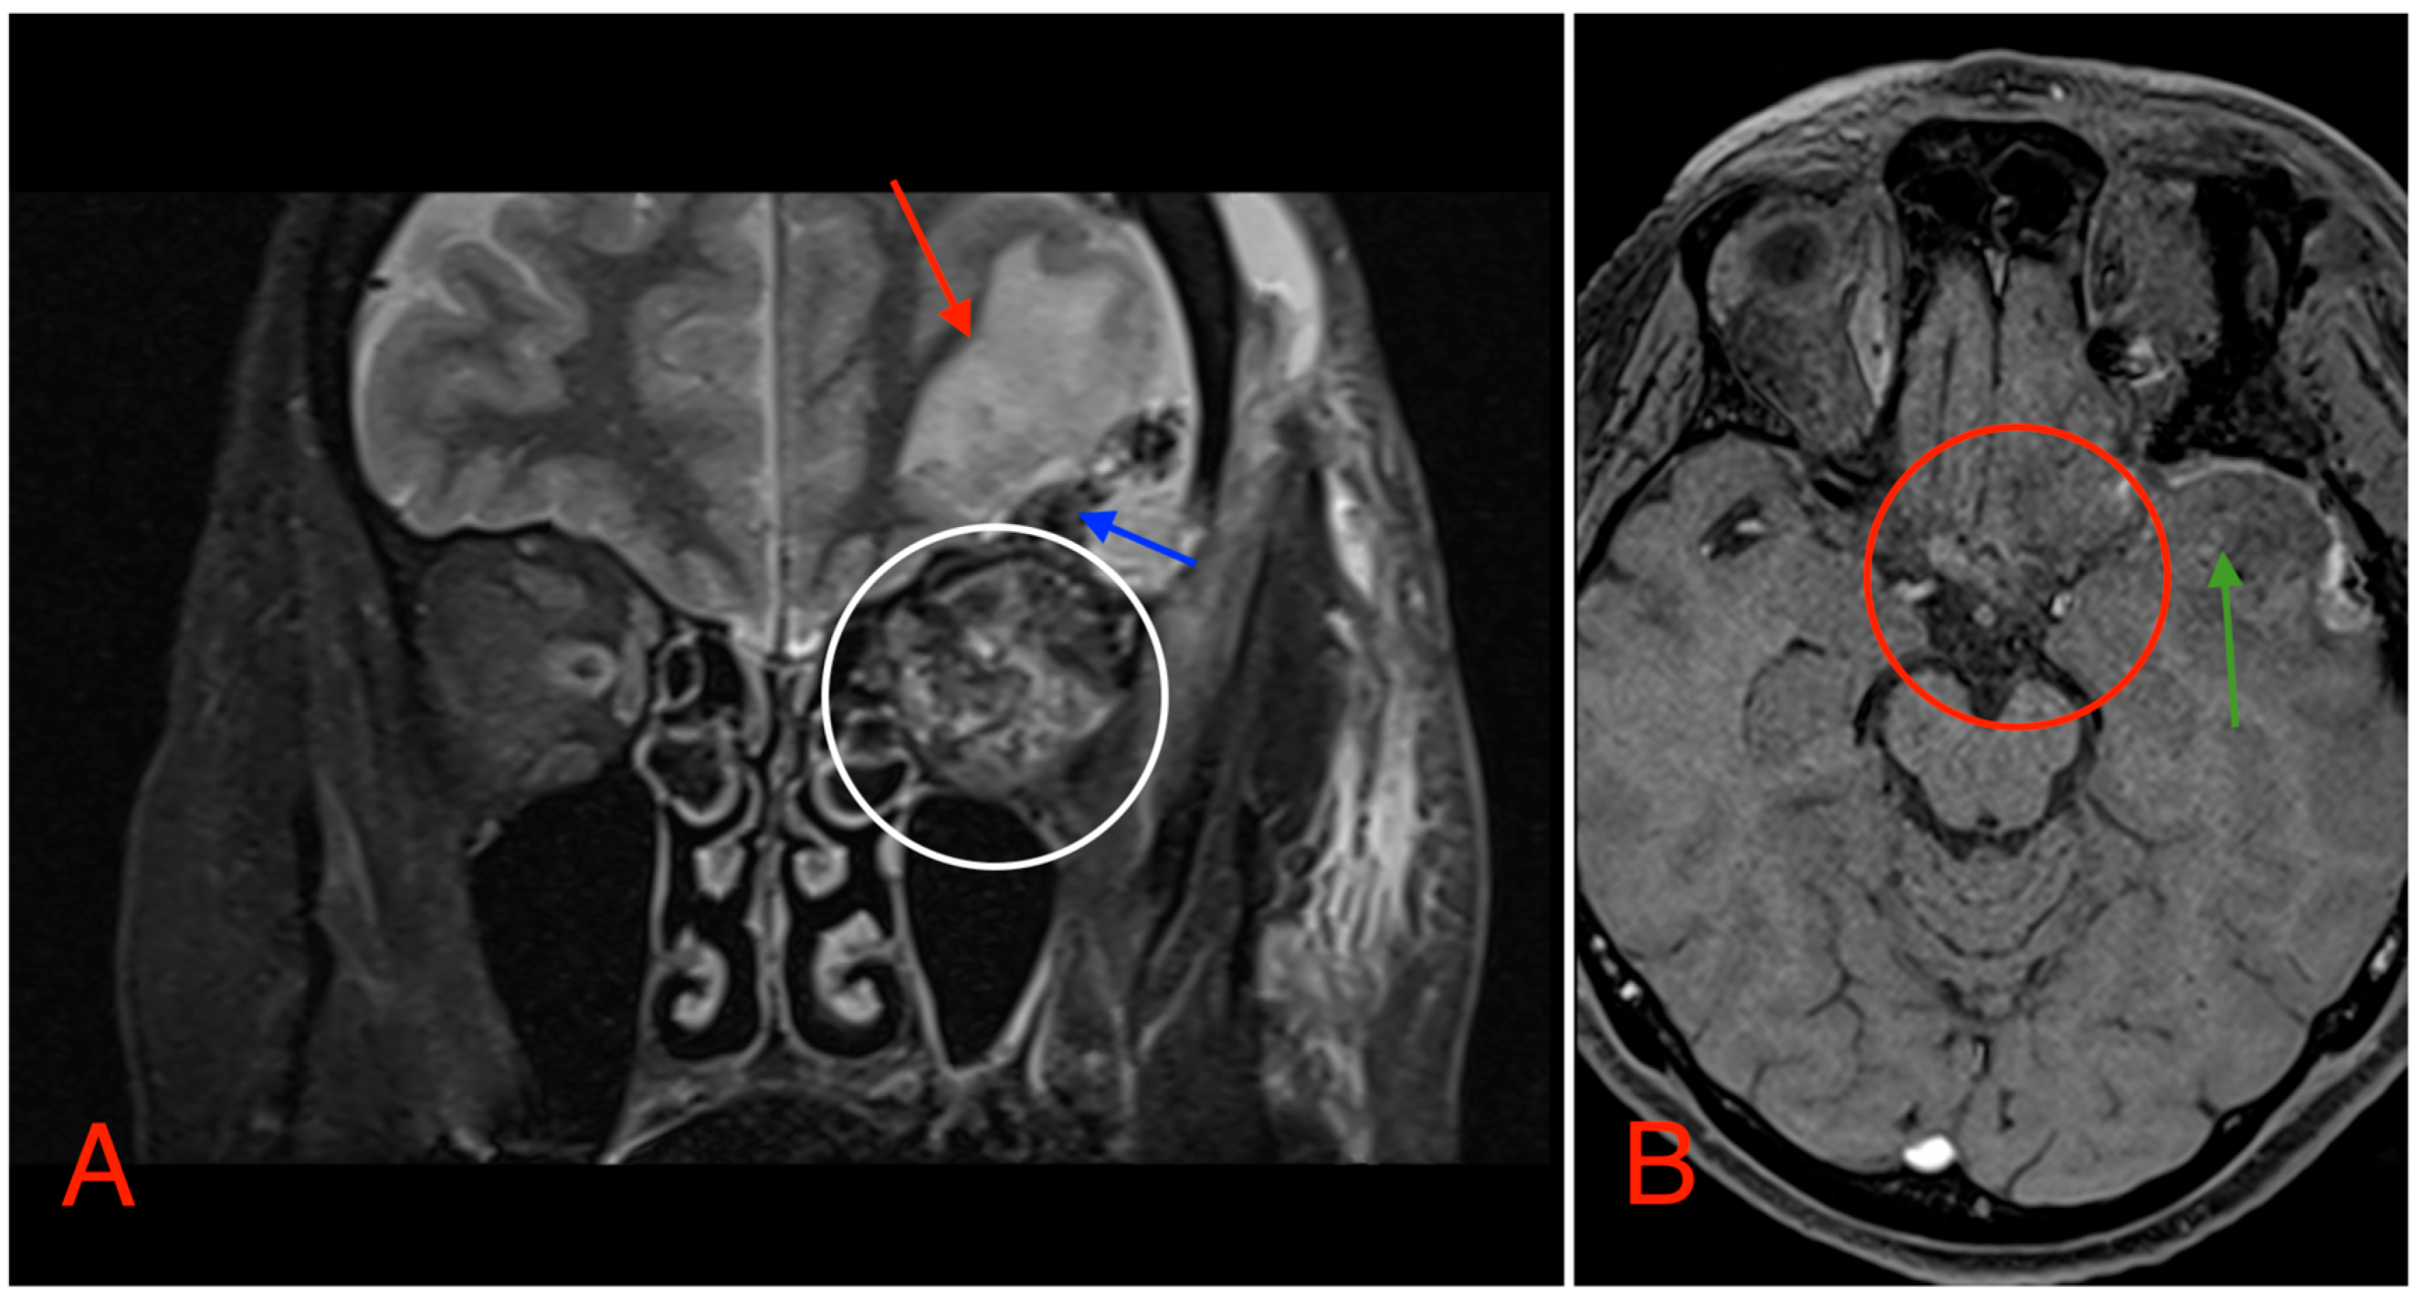

Postoperative head MRI showed partial resection of the left optic nerve. Residual tumor tissue and edema were noted in the left retrobulbar space, extending into the left prechiasmal space and into the left side of the optic chiasm (Figure 8).

Figure 8. (A) MRI image, T2 TSE STRI sequence, of the aftermath of the left-sided pterional craniotomy, showing postsurgical edema (red arrow) with a small hemorrhagic component (blue arrow). Postsurgical changes in the intraconal space can also be noted, showing an edema and a hemorrhage (white circle). (B) MRI image, T1 vibe post-gadolinium image sequence, showing postsurgical changes in the region of the optic chiasm with partial (subtotal) tumor resection (red circle). Local brain edema with hemorrhagic component (green arrow) can also be noted.